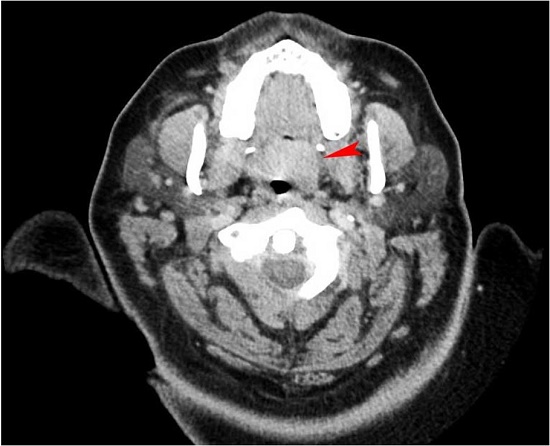

The current computed tomography (CT) of the soft tissue of the neck with contrast demonstrated a mildly enhancing soft tissue mass in the soft palate measuring 15 × 19 mm and significant fatty replacement of the parotid glands. The submandibular glands appeared symmetric with no lymphadenopathy (Figure 1).